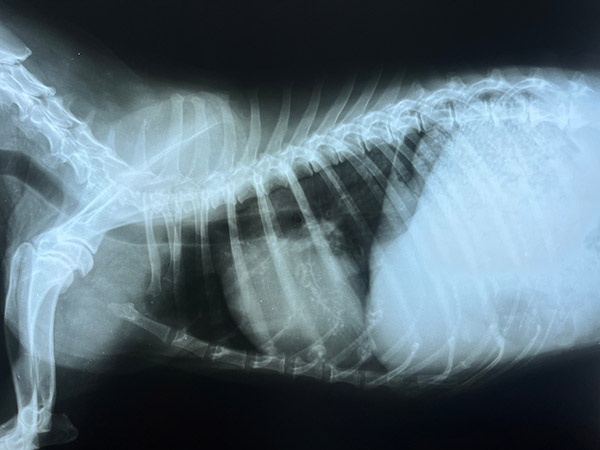

Diagnostics & Digital Radiology

At Cranford Animal Hospital, we are dedicated to offering advanced diagnostic services tailored to your pet’s needs, whether for urgent or chronic conditions. Our in-house diagnostic tools allow us to obtain quick, accurate results, providing timely insights into your pet’s health. We ensure the reliability of our lab results through careful verification and review, with digital images being analyzed by a radiologist to guarantee accuracy. Additionally, we partner with leading university laboratories for specialized testing. This comprehensive approach ensures that your pet receives the most accurate diagnoses, forming the foundation for effective treatment plans.